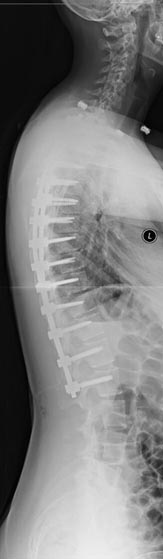

67 year old woman with Parkininsons presenting with neuromuscular kyphoscoliosis with inability to stand and look upright. Patient expressed that she was tired of talking to other people’s belly buttons.

T2 to sacrum/pelvis spinal fusion. Patient is pain free and able to stand upright and walk normally for the first time in years.